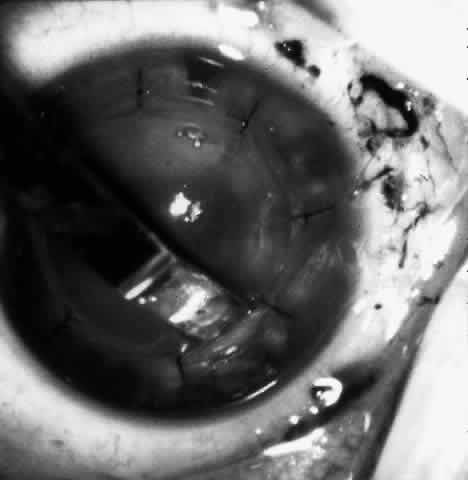

Fig. 4. Same patient as in Figure 11, with epikeratophakia lenticule in place 3 months after surgery. (Morgan KS, Ellis GS, Marvelli TL, Arffa RC: Epikeratophakia in children. with traumatic cataracts. J Pediatr Ophthalmol Strabismus 23:108–113, 1986)